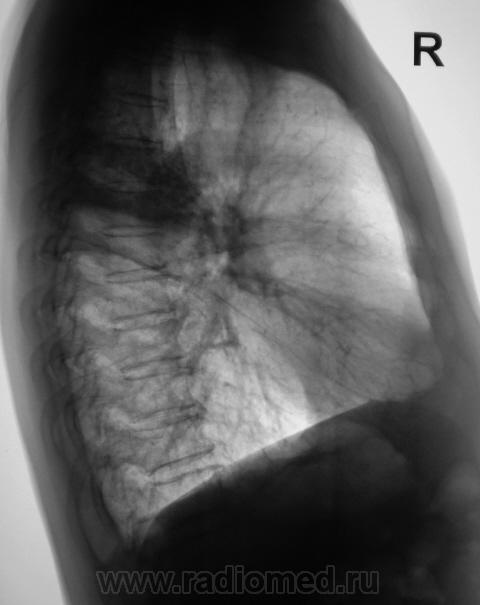

Произведена рентгенограмма в прямой стандартной проекции и томограммы в стандартных срезах.

Пациент 4 месяца, по полной программе отлежал в областной конторе, ЦВК утвердило «инфильтративный». После выписки был направлен под надзор фтизиатра по месту жительства. Ниже иллюстрации после выписки.

Снимки сегодня.

Хорошая динамика, практически все рассосалось.